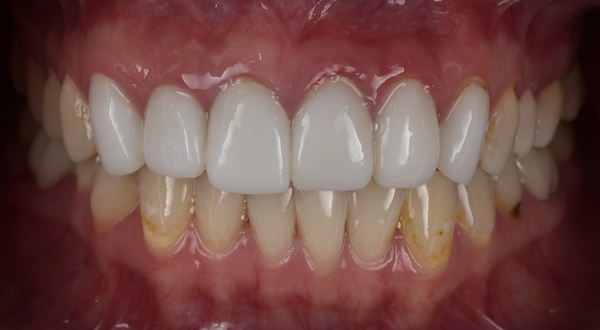

セラミック治療の治療例です。「以前、他院で治療した前歯の被せものの色味が不自然で気になる。また、被せものを入れてから歯茎が腫れるようになった。」とのことでご相談に来院されました。口腔内を確認したところ、セラミックの色が周囲の歯と調和しておらず、歯と歯茎の境目(マージン)部の適合が十分でないため、歯茎の炎症が起きている可能性が考えられました。当院にて、装着されていたセラミックの被せものを一度外し、歯茎の状態を確認したうえで、周囲の歯と自然になじむ色調のセラミックの被せものを新しく作り直しました。治療後は歯茎の腫れも落ち着き、前歯の色も周囲の歯となじみ、自然な見た目になりました。

治療後